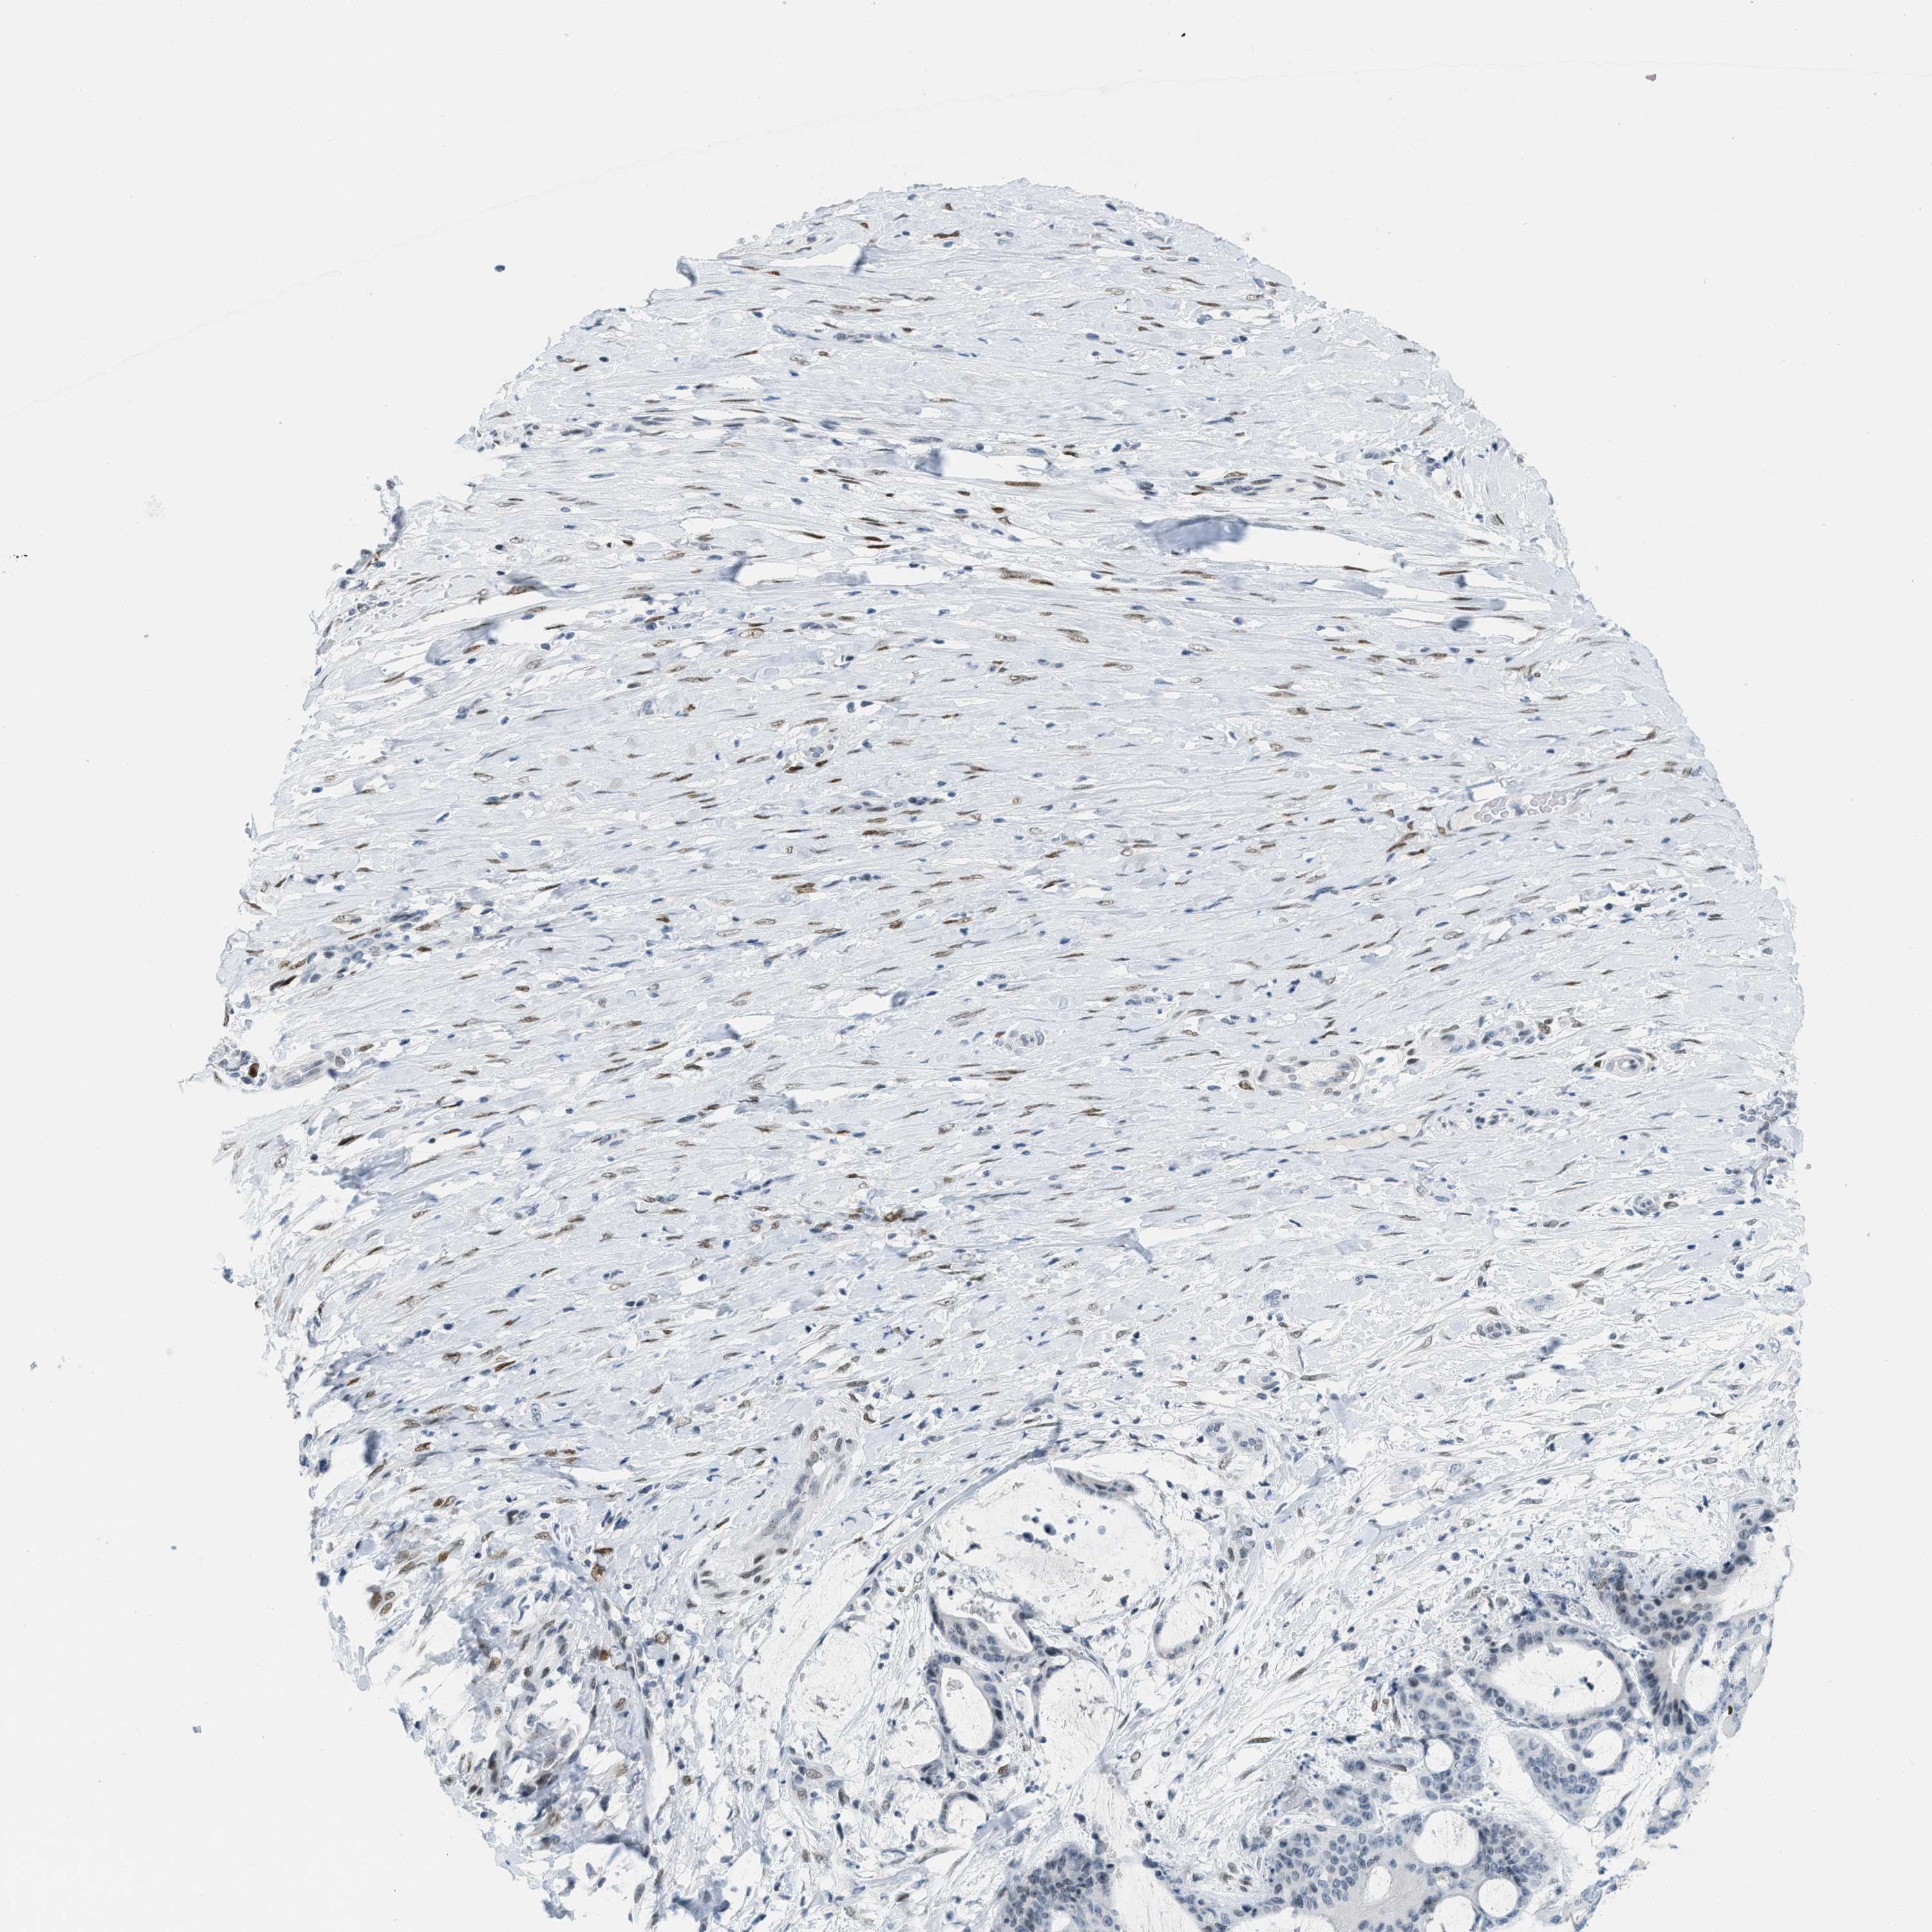

LIVER CANCER - Protein expressioni

A mouse-over function shows sample information and annotation data. Click on an image to view it in a full screen mode. Samples can be filtered based on level of antibody staining by selecting one or several of the following categories: high, medium, low and not detected. The assay and annotation is described here.

Note that samples used for immunohistochemistry by the Human Protein Atlas do not correspond to samples in the TCGA dataset.

Antibody stainingi

Antibody staining in the annotated cell types in the current human tissue is reported as not detected, low, medium, or high, based on conventional immunohistochemistry profiling in selected tissues. This score is based on the combination of the staining intensity and fraction of stained cells.

Each image is clickable and will lead to virtual microscopy that enables deeper exploration of all samples and also displays staining intensity scores, fraction scores and subcellular localization as well as patient and tissue information for each sample.

Antibody HPA003505

Antibody HPA003881

Antibody CAB018768

Staining

High

Medium

Low

Not detected

Intensity

Strong

Moderate

Weak

Negative

Quantity

>75%

75%-25%

<25%

None

Location

Nuclear

Cytoplasmic/membranous

Cytoplasmic/membranous,nuclear

Carcinoma, Hepatocellular, NOS

Cholangiocarcinoma